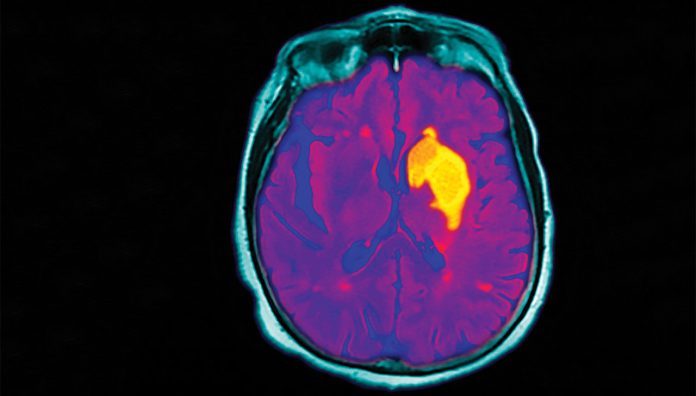

An RMH trial will test whether the time window for tenecteplase thrombolysis can be abandoned, and brain imaging (to check for salvageable healthy brain tissue) used to better predict who can still benefit from thrombolysis up to 24 hours after having a stroke.2